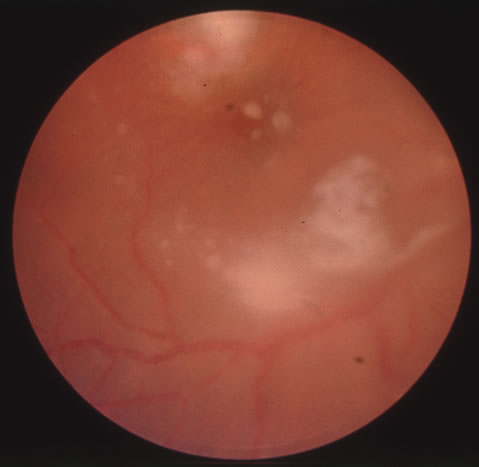

In primary ocular HSV infections, a severe follicular conjunctivitis with regional adenopathy is present. Vesicles may appear on the eyelid skin or lid margin, producing blepharitis (Fig. 3). Corneal involvement initially takes the form of a superficial punctate keratitis, which may progress to dendritic or geographic ulceration. Stromal infiltrates and uveitis are less common and relatively mild in primary disease. In uncomplicated cases, lesions usually heal completely in 2 to 3 weeks without scarring. Most cases of ocular HSV are recurrences. Recrudescent ocular herpes may take the form of dendritic or geographic ulcers, recurrent erosions, interstitial or disciform stromal keratitis, and anterior uveitis.3 HSV may also be an agent of retinitis and acute retinal necrosis (Fig. 4).

Fig. 4. Acute retinal necrosis in the fundus. Note the widespread nature of the involvement.